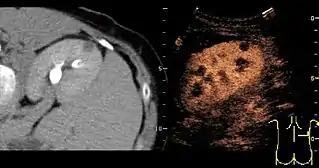

- Lesion Characterization: contrast-enhanced ultrasound plays a role in the differentiation between benign and malignant focal liver lesions. This differentiation relies on the observation[15] or processing[16][17] of the dynamic vascular pattern in a lesion with respect to its surrounding tissue parenchyma.